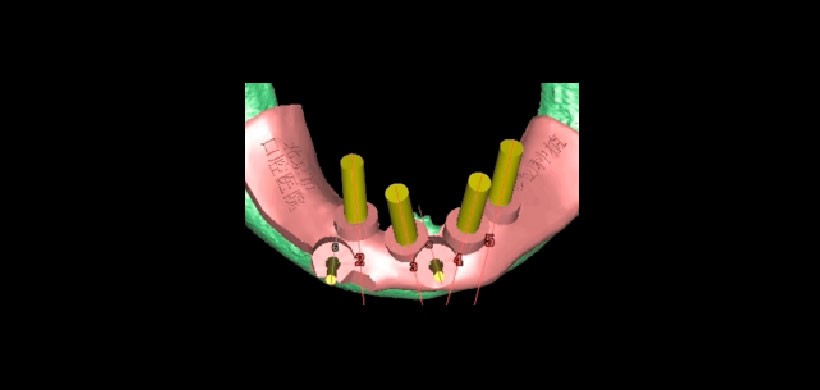

Fig 2. Diseño de la guía quirúrgica asistido por ordenador.